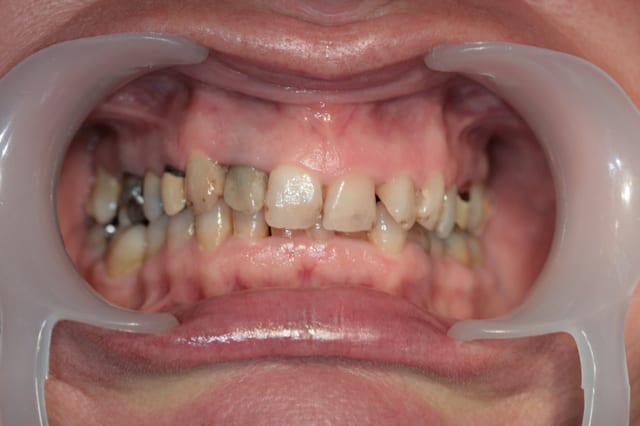

Récemment Céramik râlé, parce qu'il n'y avait pas de nouveau cas (esthétique je crois) à se mettre sous la dent. Je me jettes à l'eau avec ce dernier cas posé ce vendredi (y'a pas plus frais), une larme à l'oeil parce qu'il s'agit aussi du dernier gros cas dans mon cabinet que je quitte cette semaine pour rejoindre ma belle et nos p'tits bouts loin la bas dans le sud.

La patiente a un sourire très médiocre avec migration de plus en plus marqué du bloc incisivocanin sup. Comment l'aidez vous?

Et pourtant ça faisait un moment que je la poussais pour s'y mettre, donc ce que tu vois sur les photos c'est le résultat de la politique de soins à la française, cela dit en passant le meilleur système de santé du monde, la classe quoi!